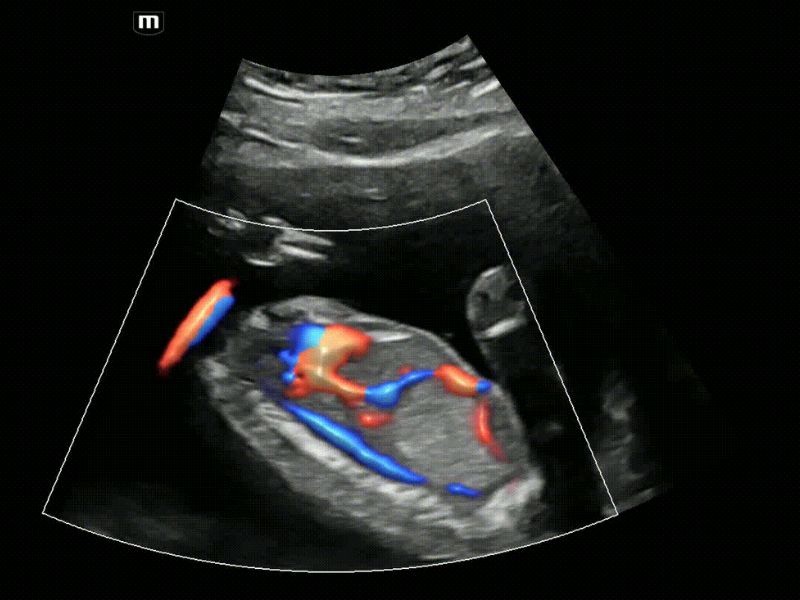

Análise de receptividade endometrial inteligente - Smart-V Trace

O Smart-V Trace detecta efetivamente estruturas anatômicas mesmo com limites fracos, como o endométrio. Além disso, ele fornece uma avaliação abrangente da pegada vascular e a intensidade do fluxo sanguíneo na área alvo é fornecida para apresentar mais informações diagnósticas para receptividade endometrial e distribuição do fluxo sanguíneo do tumor.